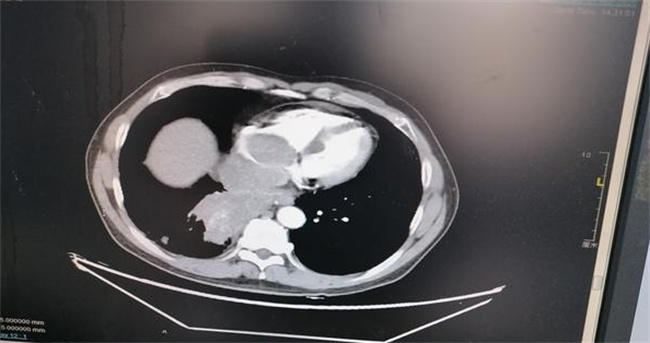

在患有新冠之后,如果没有任何的症状,这就被称之为无症状。有症状的主要就是发热,咽喉疼痛咳嗽等等。根据症状的轻重也可以分成多种,一般症状全部都是在上呼吸道,比如咽喉疼痛,发热咳嗽,流鼻涕,鼻塞,但没有出现肺部影像学的变化。

可如果有上呼吸道症状的同时还出现肺炎的表现,这就说明是普通型。如果氧饱和度明显低于93,有明显的胸闷等症状,这就属于一种危重型。